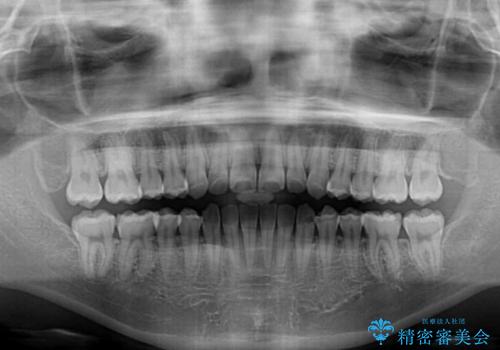

- 上下のデコボコと奥歯の咬みにくさを気にして来院された患者様です。

上顎骨の幅が下顎骨よりも小さく受け口傾向であったため、拡大装置により上顎骨の骨幅を広げて上下関係を改善し、その後インビザラインにて歯並びを整えることとしました。

下顎歯列は上顎歯列内に収まるように並んでいますが、上顎骨の幅が狭いと、下顎臼歯が全体的に舌側に傾斜した歯列となってしまいます。

舌側に傾斜した歯列は奥歯に力の負担がかかりやすく、歯磨きがしにくいなどの問題があるため、上顎骨拡大により舌側傾斜を改善することが可能となります。